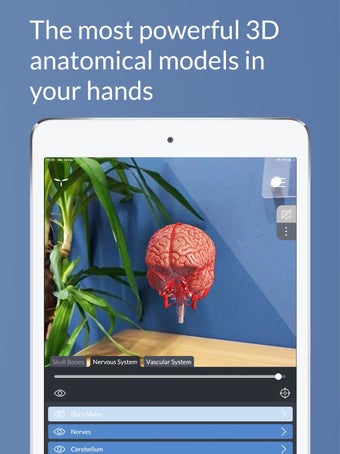

Además, el módulo "ARTouch" de esta aplicación te permite ver la neuroanatomía de manera híbrida utilizando el modelo físico AnatomyTouch.

De esta manera, puedes experimentar la belleza y precisión del modelo, lo que te permite estudiar y comprender el cerebro humano de una manera única y personal.